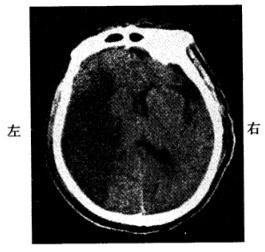

男,60岁。早晨睡醒后左侧肢体无力,刷牙时无法拿杯子。有糖尿病和高血压病史,无心脏病史。半天后到急诊就诊。查体:左侧肢体肌力3级,腱反射高于右侧,左侧Babinski征阳性。左侧肢体痛温觉减退。脑CT见图示:

患者可能的诊断为

A脑转移癌

B脑栓塞

C短暂性脑缺血发作

D脑血栓形成

E高血压性脑出血